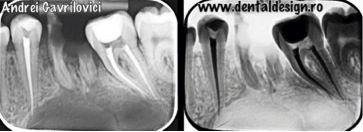

În acest articol vom prezenta intervenția chirurgicală pentru extirparea chistului aferent primului molar inferior de pe partea stângă. Dupa consultul chirurgical s-a decis efectuarea tratamentelor de canal la dinții care sunt prinși în formațiunea chistică, urmând ca porțiunea din rădăcină care este infectată să fie îndepărtată pentru a preveni contaminarea întregului dinte.

Intervenția chirurgicală a durat aproximativ două ore, a fost necesar un lambou trapezoidal prin care s-a dat la o parte gingia de pe os din dreptul caninului până în dreptul ultimului molar pe partea stângă. După aceea s-a extras restul radicular care a cauzat infecția, s-a frezat din osul vestibular și s-a îndepărtat formațiunea chistica. Concomitent s-a realizat rezecția dinților ale căror rădăcini au fost prinse în chist și s-a realizat adiția osoasă și repoziționarea gingiei cu ajutorul firelor de sutură.

*rezectia apicală: porțiunea din rădăcina colorată în roșu a trebuit îndepărtată deoarece era prinsă în procesul infecțios